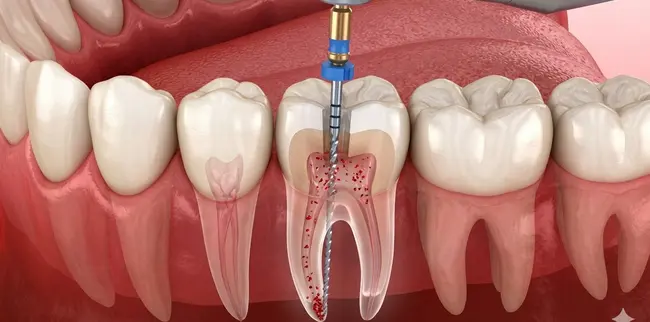

Endodontic therapy

A root canal is a precise procedure to take out inflamed or infected pulp — the soft inner tissue containing nerves and blood vessels — deep inside the tooth.

Dr. Soyfer then cleans each root canal and shapes it to leave the best opening for disinfecting, where she kills any bacteria in the canals and fills them with a safe, biocompatible material that seals them off.

The procedure is concluded with a strong crown or filling, which restores the tooth to its inherent strength and function. These days, thanks to precise toolwork, digital imaging and effective local anesthesia, most patients visiting our Arlington office are surprised at how extremely comfortable the procedure is — often reporting that for them the greatest advantage of their experience was finding quick relief from chronic pain.

The infected pulp is removed, canals shaped and disinfected from all bacteria.